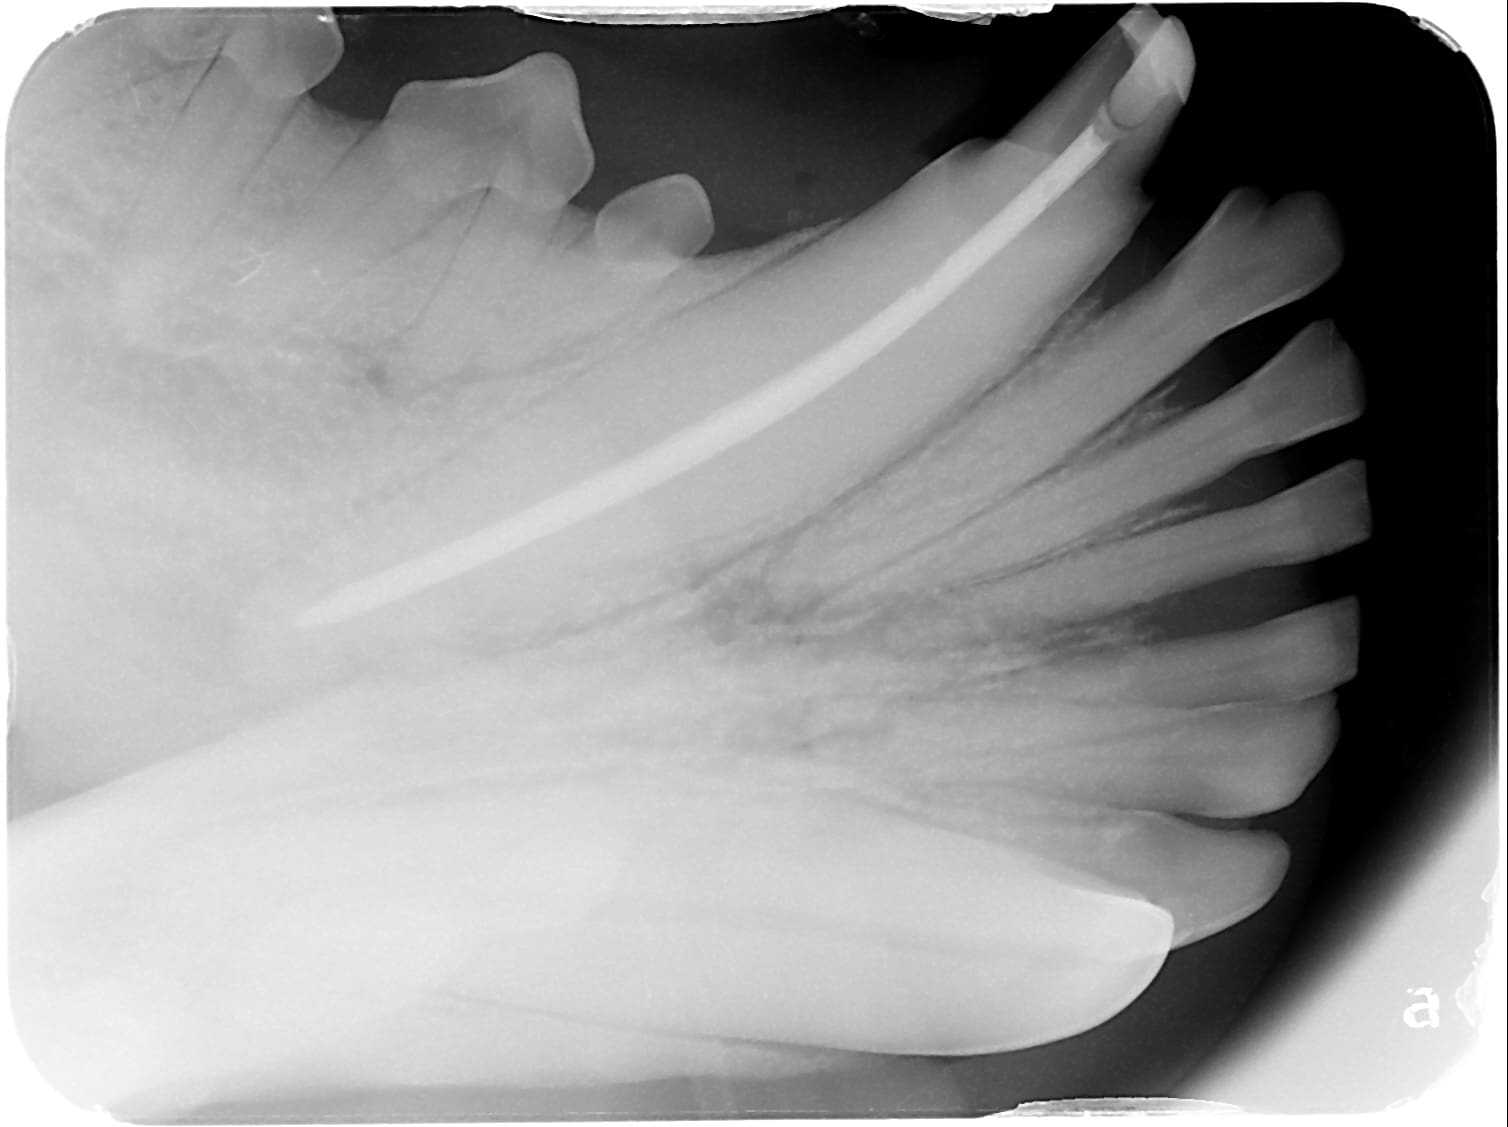

Endodontic therapy, commonly known as root canal therapy, offers a highly successful solution for saving damaged teeth in dogs and cats. When performed by a board-certified veterinary dentist and oral surgeon, root canal treatment in dogs achieves a success rate of approximately 96% (including cases with no evidence of failure).

The board-certified veterinary dentists and oral surgeons at Carefree Dentistry and Oral Surgery for Animals in Phoenix, AZ, have successfully performed hundreds of these advanced procedures. Root canal therapy is typically recommended for non-vital (discolored) teeth or fractured teeth with exposed pulp.

Inside every tooth lies a central canal that contains the tooth’s blood supply and nerves. This soft tissue is called the pulp. When the pulp becomes infected or dies due to trauma or decay, root canal therapy becomes the treatment of choice.